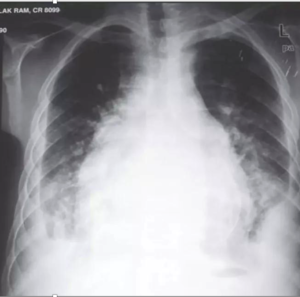

• ⁠ ⁠Xray showing cavitatory consolidation in right upper lung zone and multiple ill-defined nodules in both lungs

CAVITATION AND TREE IN BUD SIGN IS INDICATIVE OF AN ACTIVE DISEASE PROCESS AND USUALLY HEALS S A LINEAR OR FIBROTIC LESION.